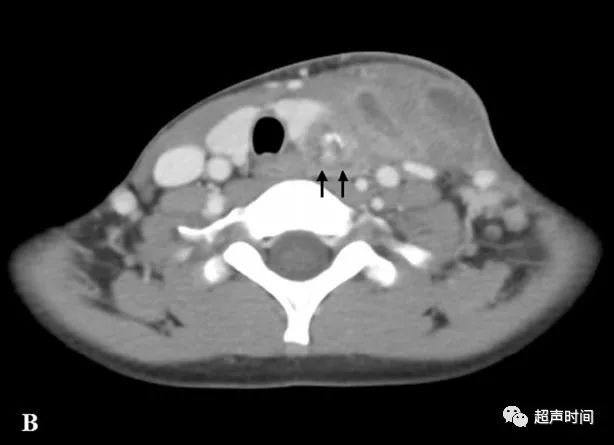

超声高手进阶累及甲状腺的梨状隐窝瘘

甲状软骨 食管

舌骨体4 会厌前间隙5 下颌下腺6 喉咽8 梨状隐窝9